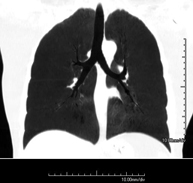

- Tórax

- TC Tórax

Prueba diagnóstica que consiste en obtener imágenes del tórax de alta definición anatómica (pulmones, corazón, mediastino, grandes vasos, caja torácica, etc.) mediante el empleo de un equipo de TC (Tomografía Computarizada). Dichas imágenes se estudian posteriormente en una estación de trabajo que permite reconstrucciones bidimendionales en diferentes planos del espacio y también reconstrucciones 3D (volumétricas). Algunos estudios requieren el empleo de contraste yodado para mejorar la definición de las imágenes.

Prueba diagnóstica que consiste en obtener imágenes del tórax de alta definición anatómica (pulmones, corazón, mediastino, grades vasos, caja torácica, etc.) mediante el empleo de un equipo de TC (Tomografía Computarizada). Dichas imágenes se estudian posteriormente en una estación de trabajo que permite reconstrucciones bidimendionales en diferentes planos del espacio, y también reconstrucciones tridimensionales (3D: volumétricas). Algunos estudios requieren el empleo de contraste yodado para mejorar la definición de las imágenes.